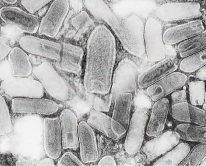

| Ο ιός της λύσσας όπως φαίνεται στο μικροσκόπιο |

Η λύσσα προκαλείται από ένα ραβδόμορφο ιό ο οποίος προσβάλει τον εγκέφαλο. Πιστεύεται ότι υπήρχε από το 2300 π.Χ. στη Μεσοποταμία. Την περιέγραψε για πρώτη φορά ο Δημόκριτος το 500 π.Χ. Ο Αριστοτέλης το 400 π.Χ. επεσήμανε τη μετάδοσή της μέσω δηγμάτων. Ο ιός της λύσσας σήμερα βρίσκεται σε όλη τη Γη εκτός της Ανταρκτικής. Προσβάλλει όλα τα θηλαστικά ζώα, άρα και τον άνθρωπο, μιας και ανήκει στα θηλαστικά.